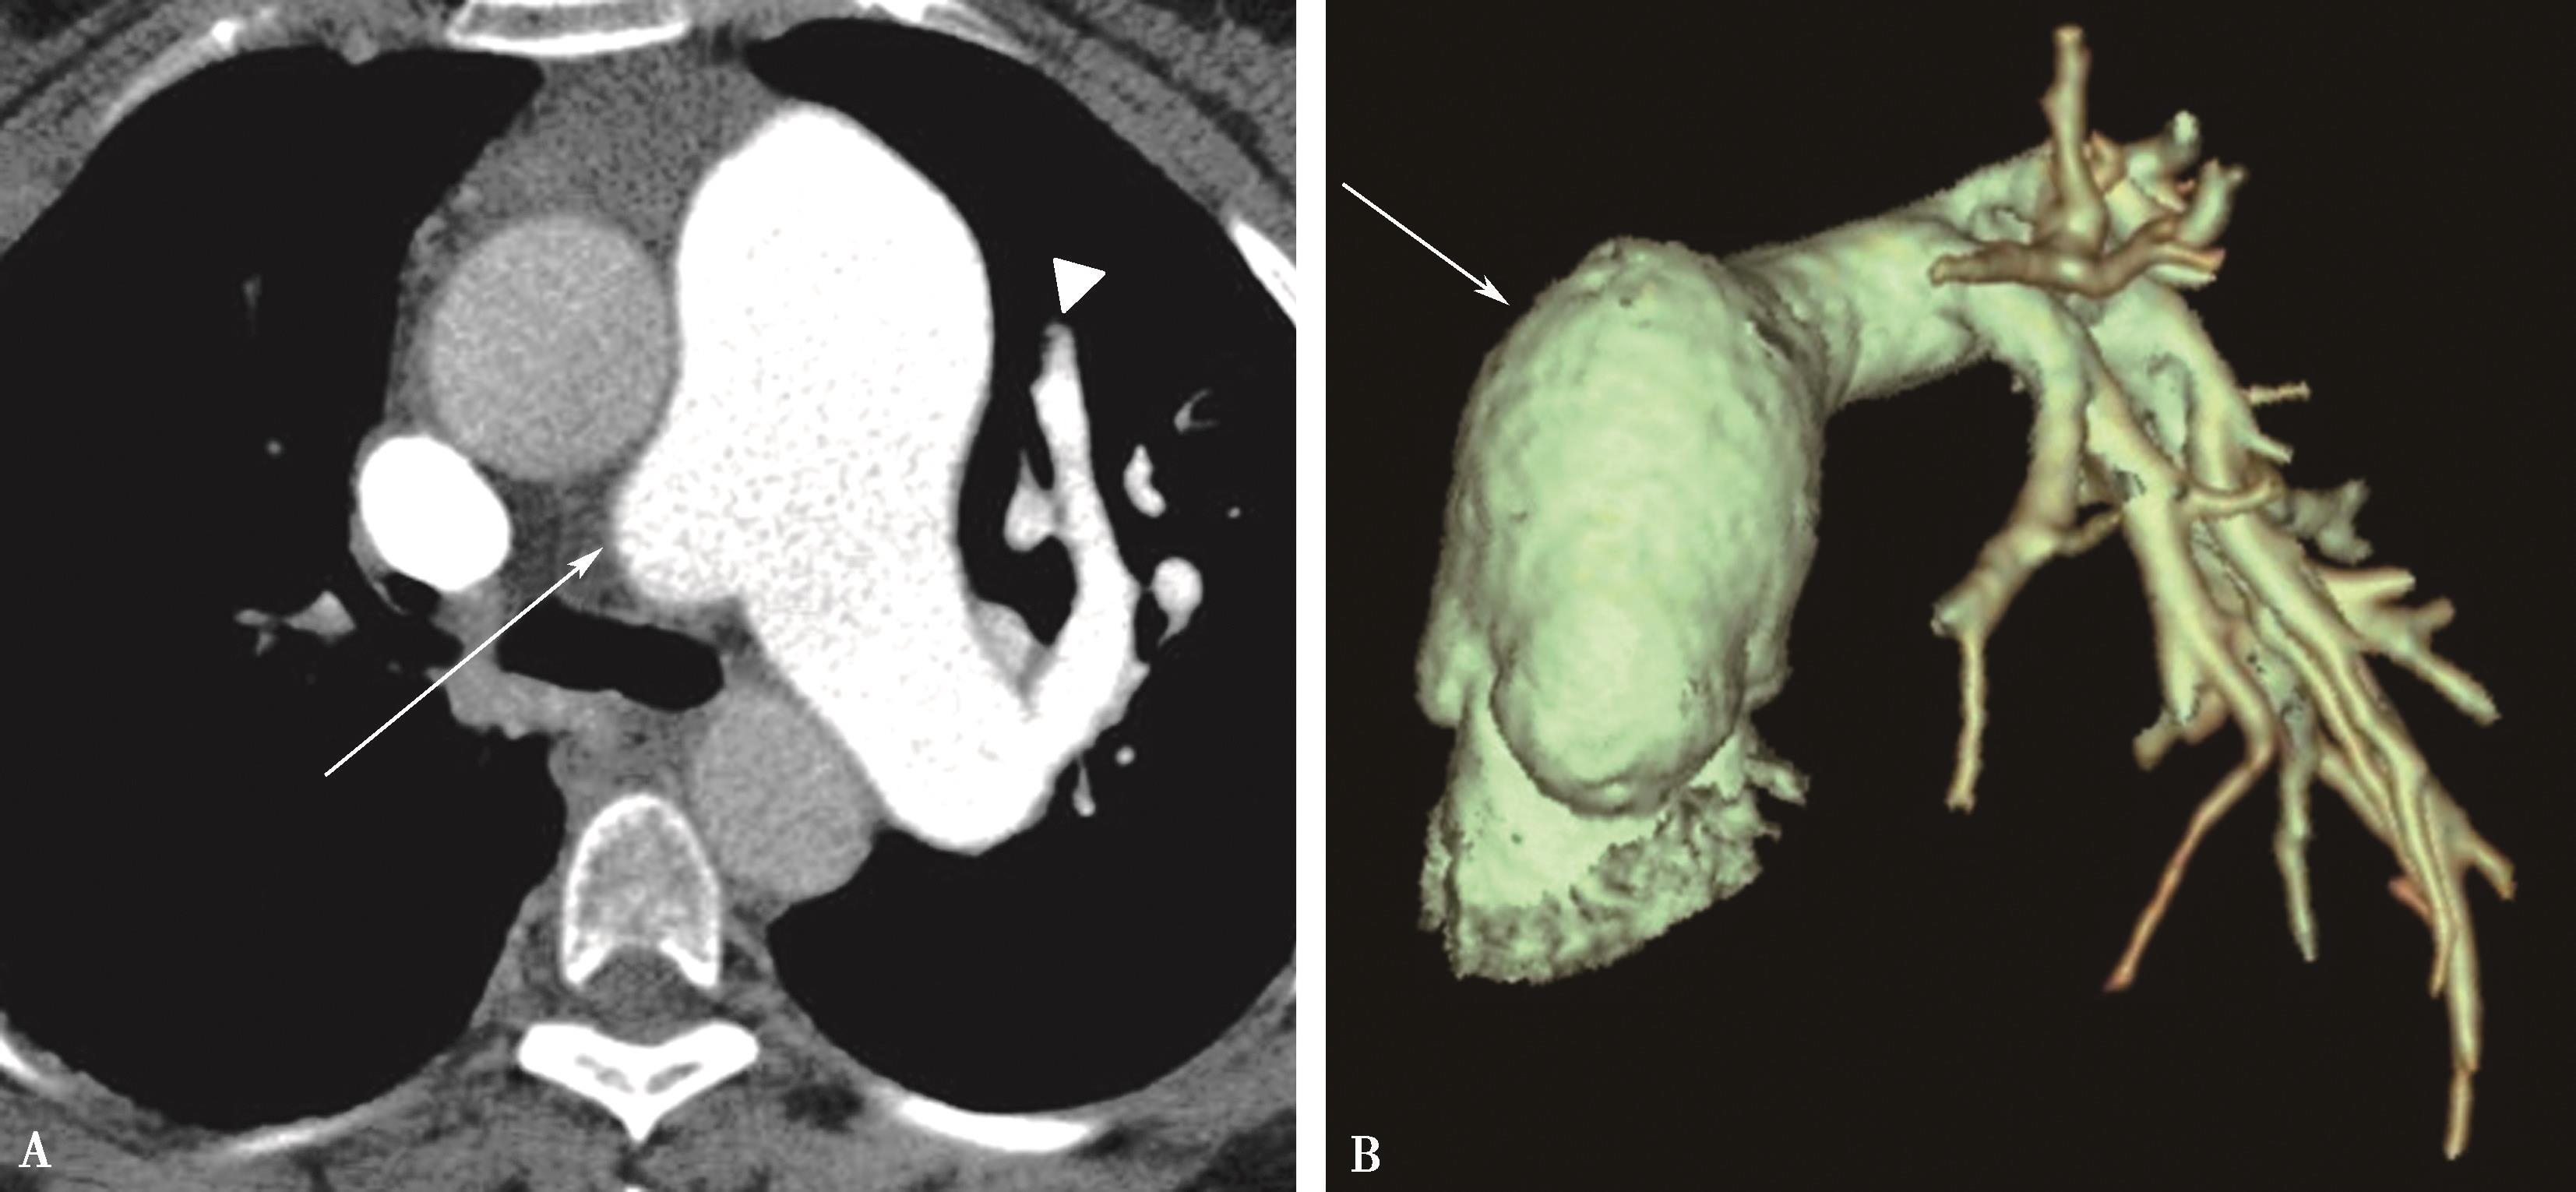

CT横断扫描。A、B.多层重组;C、D.示主肺动脉及左右肺动脉内结节状充盈缺损,可见 “指压征”(↑),右肺动脉及左下肺动脉闭塞;前上纵隔中等密度影,考虑为纵隔转移(A▲)。肺动脉造影(E)示主肺动脉不规则充盈缺损,右肺动脉及左下肺动脉闭塞,术后病理诊断:低分化平滑肌肉瘤(F)

图8-7-1 女,21岁,反复咯血2年,胸闷气短1年半

1.直接征象(图8-7-1~图8-7-3)

(1)主肺动脉或单侧肺动脉干管腔充盈缺损,大块状充盈缺损呈分叶、结节样(指压征),可以延肺动脉血管长轴向远侧蔓延。

(2)晚期肿块沿肺动脉长轴管腔膨胀性生长,可以充满主肺动脉、左右肺动脉干及叶段分支管腔,血管闭塞。CTPA检查对比剂存在于节结间呈分隔状,有一定提示。

(3)肿瘤可以发生于或累及肺动脉瓣、右心室流出道。如果有蒂存在,肿瘤可以有一定活动度。

(4)肿瘤依恶性程度,生长发展较快,肺门血管影圆隆增大,呈 “三叶草”征。

(5)远处转移:最常见的为肺和肋骨。

2.间接征象

(1)肺动脉扩张,右心房室增大,肺动脉高压。

(2)双肺实质灌注不均。